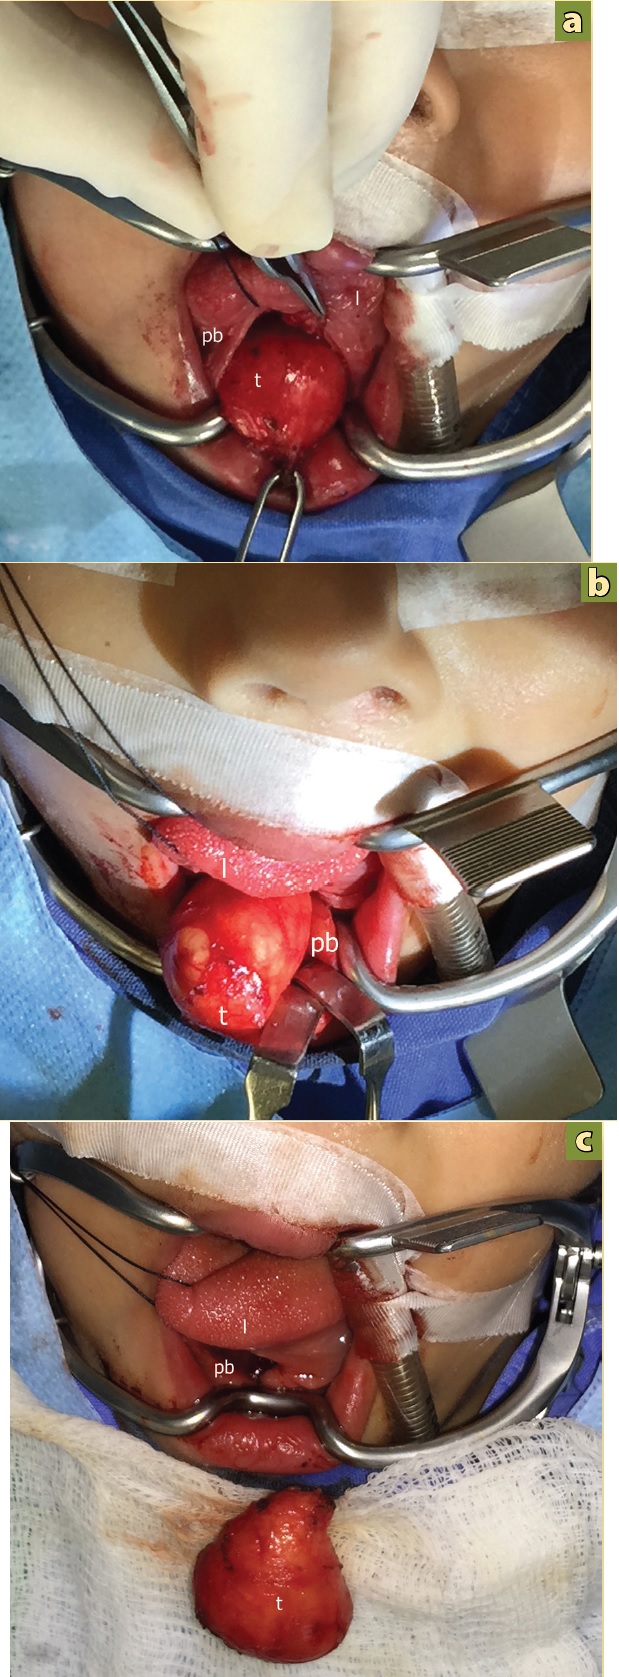

Por la evolución de la lesión y el potencial compromiso de la vía aérea, se decidió hacer tratamiento quirúrgico. Se realizó la resección quirúrgica bajo anestesia general, por abordaje transoral, realizando incisión en la línea media de la lengua, donde se localizo un tumor de aspecto quístico, de bordes bien definidos, de consistencia blanda, que se resecó por completo y sin complicaciones, (Figura 4a, 4b, 4c).

Figura 4 Resección de quiste por vía transoral. a) Incisión en línea media e identificación de conducto de Warthon derecho. b) Disección roma del tumor (t). c) Pieza final y defecto en piso de boca (pb).